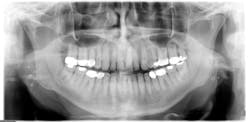

Unless the patient brings this to the attention of a health-care provider, the enlargement of the tonsil may go unnoticed until the patient is examined during an oral cancer exam or the calcifications are noticed on a panoramic radiograph. The importance of examining the tonsillar region should be emphasized not only because of entities such as tonsillitis, but also because of tonsillar cancer or other oral cancers affecting the posterior region of the mouth (see Figure 2).

Giant tonsilloliths are not common, but when very large, they may be mistaken for pathology when viewed on a radiograph. Careful clinical assessment is needed.

Radiographic assessment: Small, multiple, radiopaque, ill-defined, calcareous objects are seen on the radiograph (see Figure 1). The radiograph presented in this column was taken in 2015 of a 76-year-old male.

These opacities are not limited to the palatine tonsils but may also be seen in accessory lymphoid tissue. Sometimes what is referred to as "ghost images" appear on a pantomograph, making a pseudotonsillolith visible on the opposite side. This occurs because the object is located between the X-ray source and the center of rotation of the cassette. The patient may have oral calcifications bilaterally or unilaterally, so further evaluation is always needed.